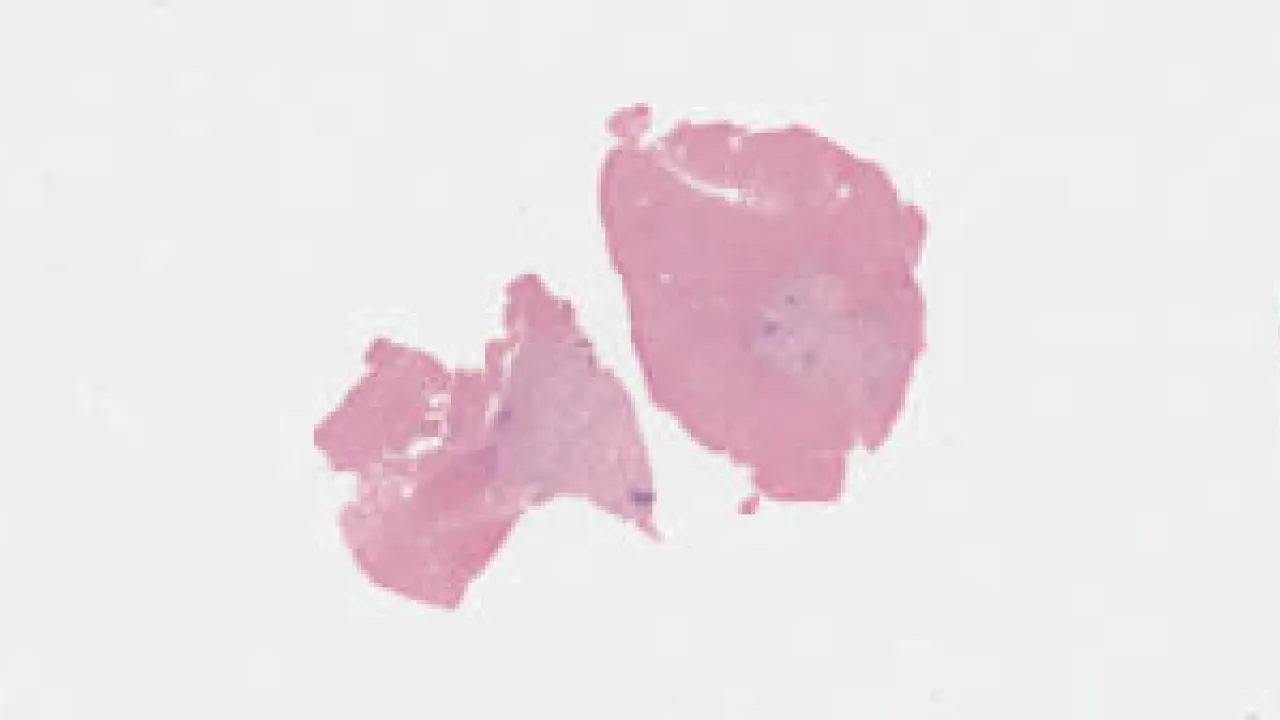

Skin, Subcutaneous Fat Necrosis